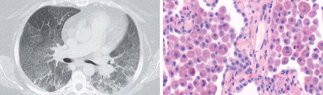

Recent studies indicate that Generative Pre-trained Transformer 4 with Vision (GPT-4V) outperforms human physicians in medical challenge tasks. However, these evaluations primarily focused on the accuracy of multi-choice questions alone. Our study extends the current scope by conducting a comprehensive analysis of GPT-4V's rationales of image comprehension, recall of medical knowledge, and step-by-step multimodal reasoning when solving New England Journal of Medicine (NEJM) Image Challenges - an imaging quiz designed to test the knowledge and diagnostic capabilities of medical professionals. Evaluation results confirmed that GPT-4V outperforms human physicians regarding multi-choice accuracy (88.0% vs. 77.0%, p=0.034). GPT-4V also performs well in cases where physicians incorrectly answer, with over 80% accuracy. However, we discovered that GPT-4V frequently presents flawed rationales in cases where it makes the correct final choices (27.3%), most prominent in image comprehension (21.6%). Regardless of GPT-4V's high accuracy in multi-choice questions, our findings emphasize the necessity for further in-depth evaluations of its rationales before integrating such models into clinical workflows.